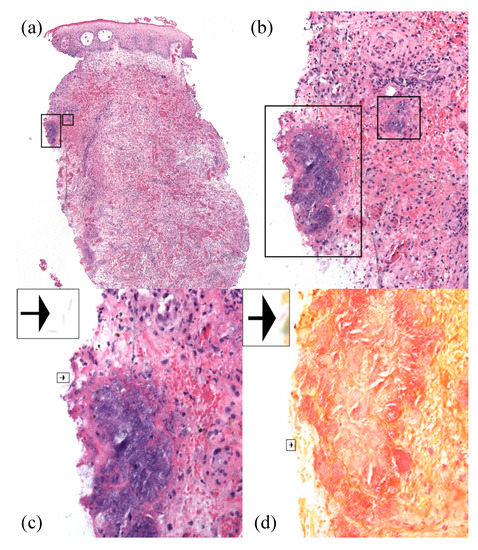

2. Case Report